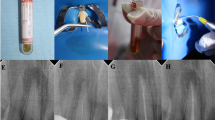

Scanning electron microscopy examination

The teeth were longitudinally grooved, sectioned, and rinsed in phosphate-buffered saline, soaked in glutaraldehyde for 1 h, and then fixed with osmium tetroxide for 30 min [30]. Samples were then dehydrated, mounted on SEM discs, and sputter coated with 5 nm of gold–palladium for conductivity, and examined with a scanning electron microscope (JEOL Model JSM 6010Plus). Representative images were taken of the middle and apical thirds at magnifications of × 500, × 1000, × 5000, and × 10,000.

Scanning electron microscopy analysis

SEM examination shows the presence of bacteria in the dentin tubules in group 1. No bacteria could be visualized in groups 2–5 (Fig. 2). These results may be due to the lower numbers of bacteria in the treatment groups and the limitations of SEM, which include processing of the samples.

The radicular dentin using SEM imaging. The radicular dentin samples were washed and fixed (as stated in the “Materials and methods” section), and then their surface topography was analyzed using scanning electron microscopy (SEM). Bar = 5 μm and × 5000 magnification. Bacteria could be visualized only in group 1, which was the positive control group

Microbiological results were verified with SEM, which showed presence of bacteria in the positive control group but absence of bacteria in the other groups (Fig. 2). Groups G3 and G4 showed positive cultures, but the SEM images did not show the presence of bacteria which could be related to the way these teeth were sectioned and processed and is one of the known drawbacks of SEM imaging [39]. SEM imaging does not help determine the viability of the bacteria and is another drawback of this technique. Hence, CLSM imaging was performed to visualize the presence of live/dead bacteria in the dentinal tubules (Fig. 3).